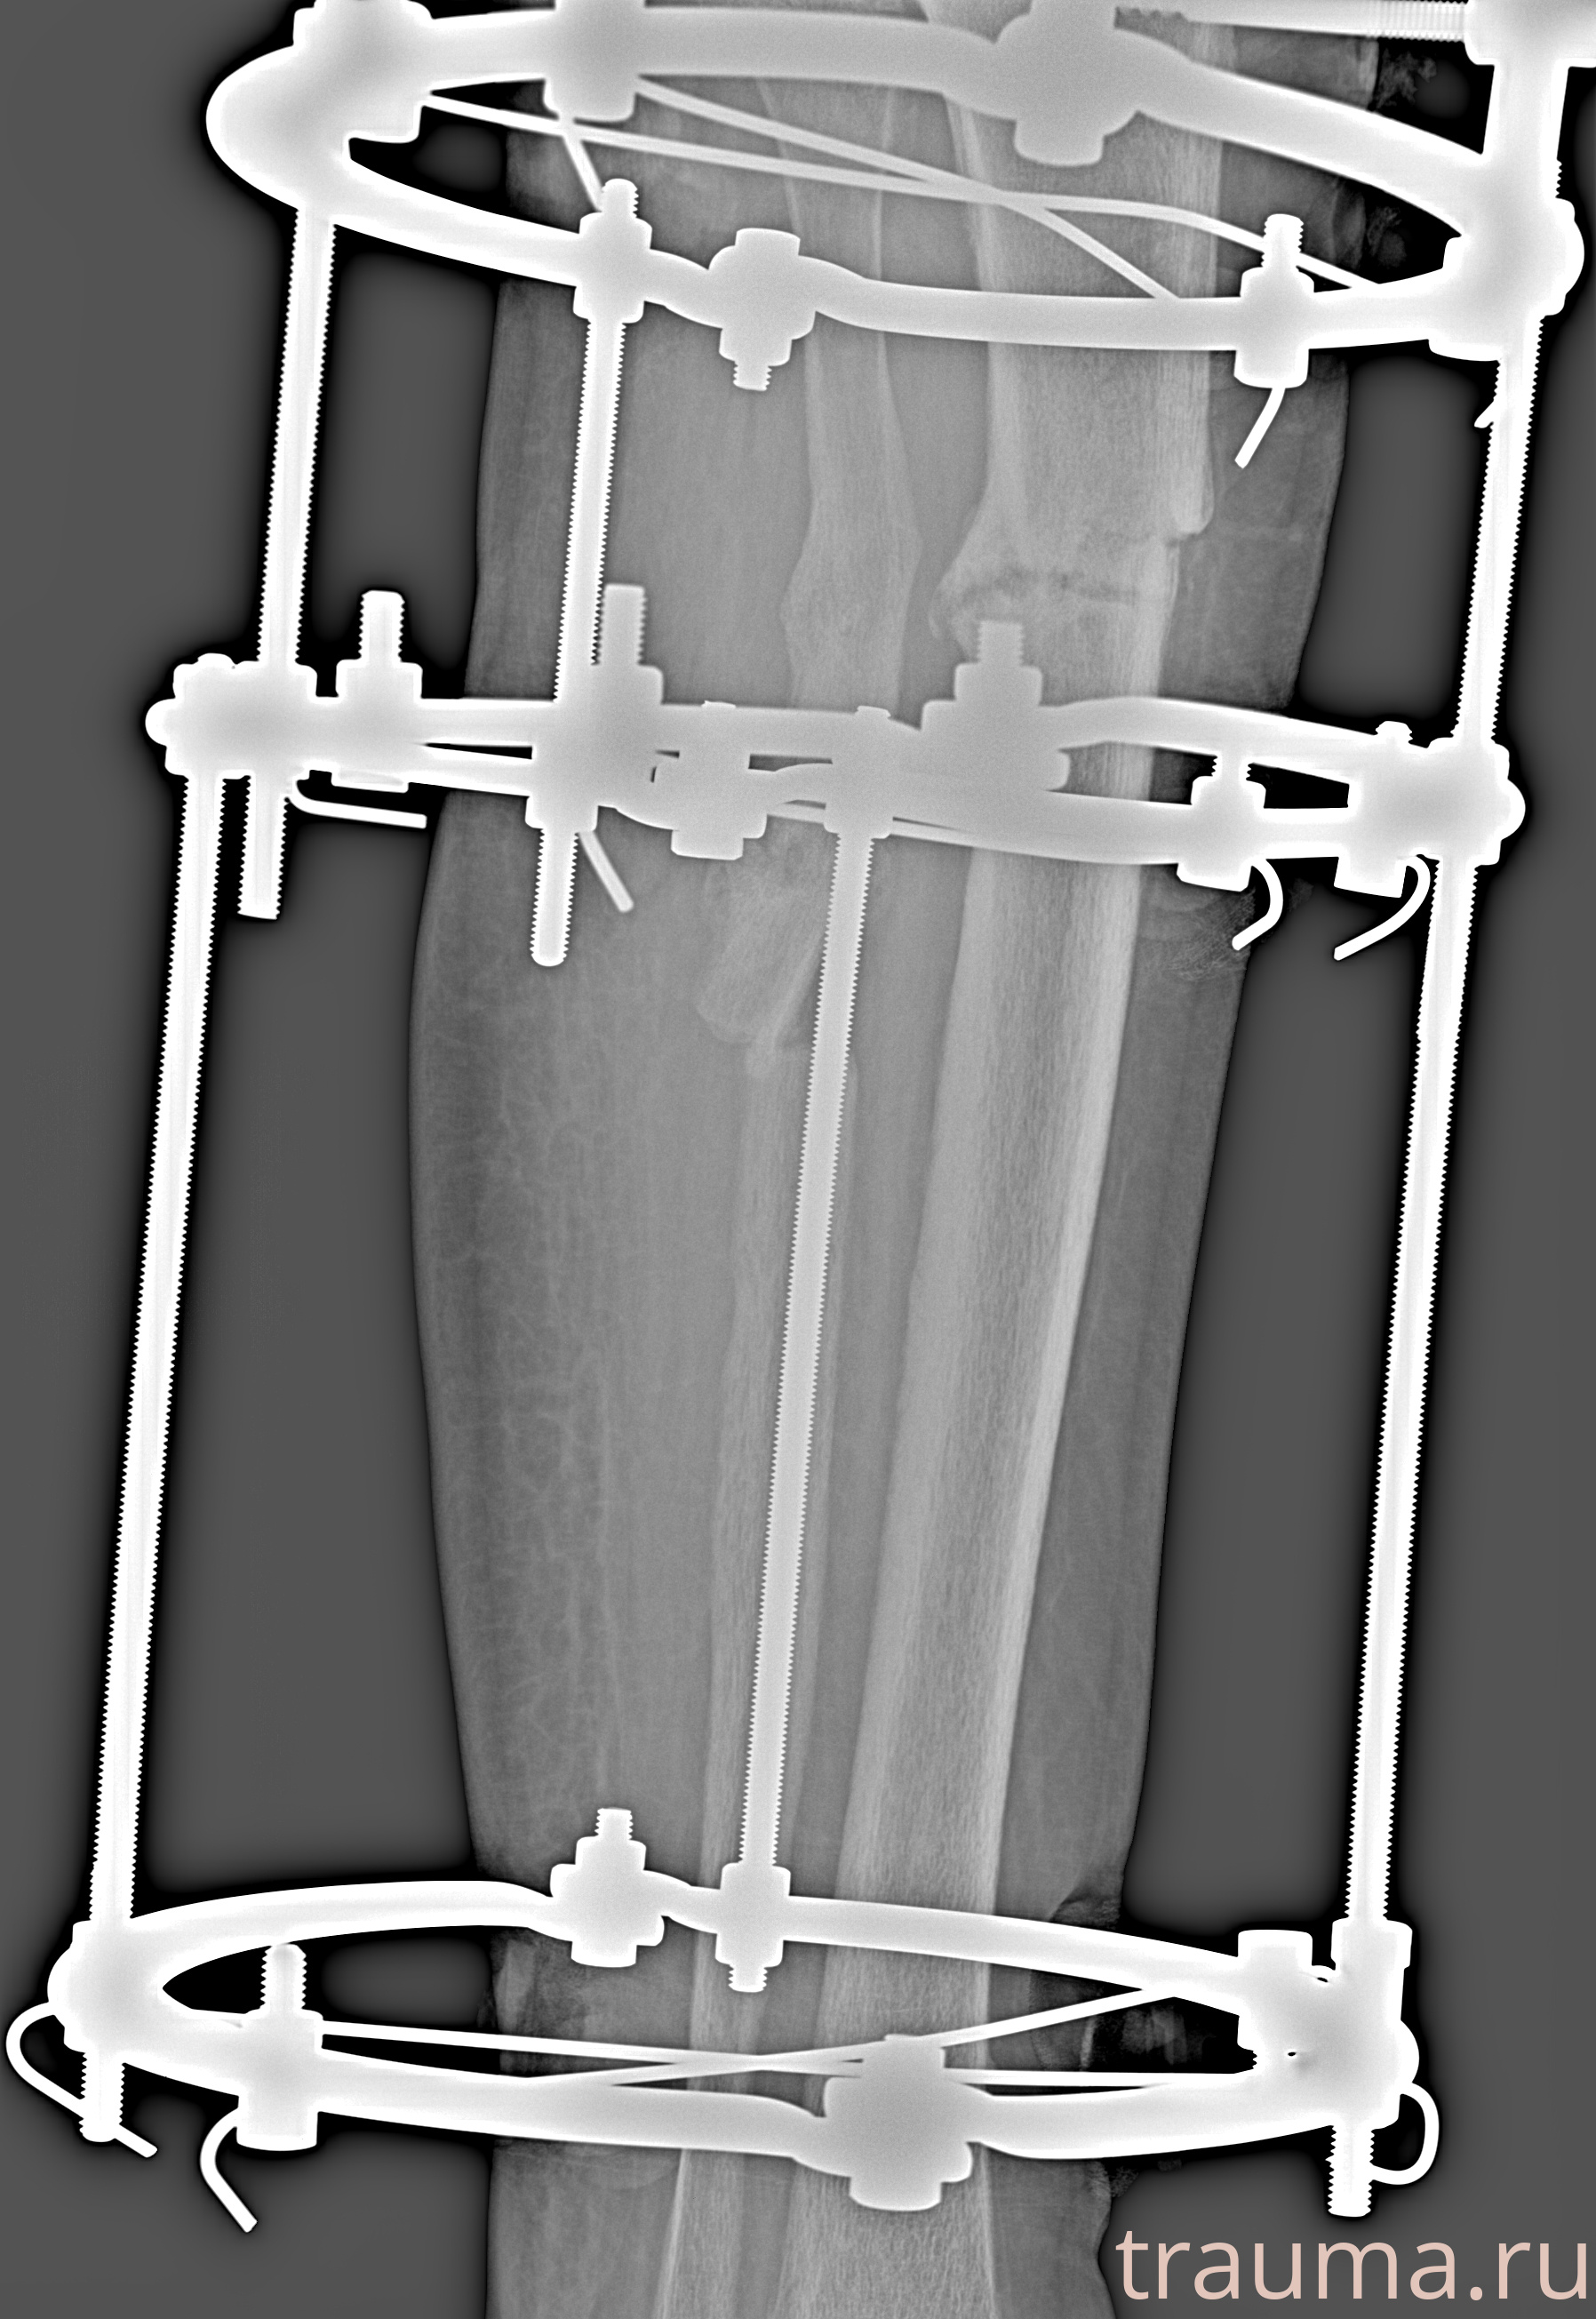

Рентгенограммы

Левая

Рентген на дому: по вашему адресу приезжает врач-рентгенолог, травматолог-ортопед с мобильным рентгеновским аппаратом, проводит диагностику травмы или заболевания, делает необходимые рентгенограммы, дает рекомендации по дальнейшему лечению. Получить качественные снимки в домашних условиях возможно благодаря уникальной методике, разработанной МосРентген Центром для института  Склифосовского